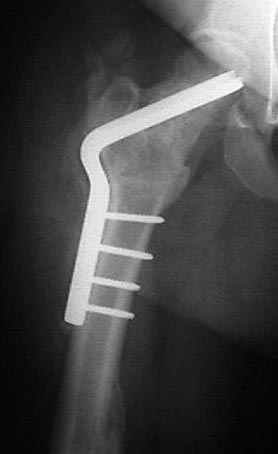

Несколько снимков из моей коллекции, чтобы разьяснить, почему мы до сих пор делаем различные варианты остеотомии.

На рисунке N1 предоперационный план лечения ложного сустава шейки бедра- линия ложного сустава, угол и направление введения импланта, клиновидная остеотомия в градусах и миллиметрах, второй снимок после коррекции, расчет, на сколько удлиняется конечность и размеры импланта;

N3 рисунок окончательный снимок, после операции моя рентгенограмма должен выглядеть примерно как эта картина. На N4 снимке клин перед удалением; N5 послеоперации 3 нед.; N6 окончательная рентгенограмма.

(доложен в Ст. Петербурге 2003 и в Москве 2004)

варус при проксимальном отделе 95 градусной пластиной.